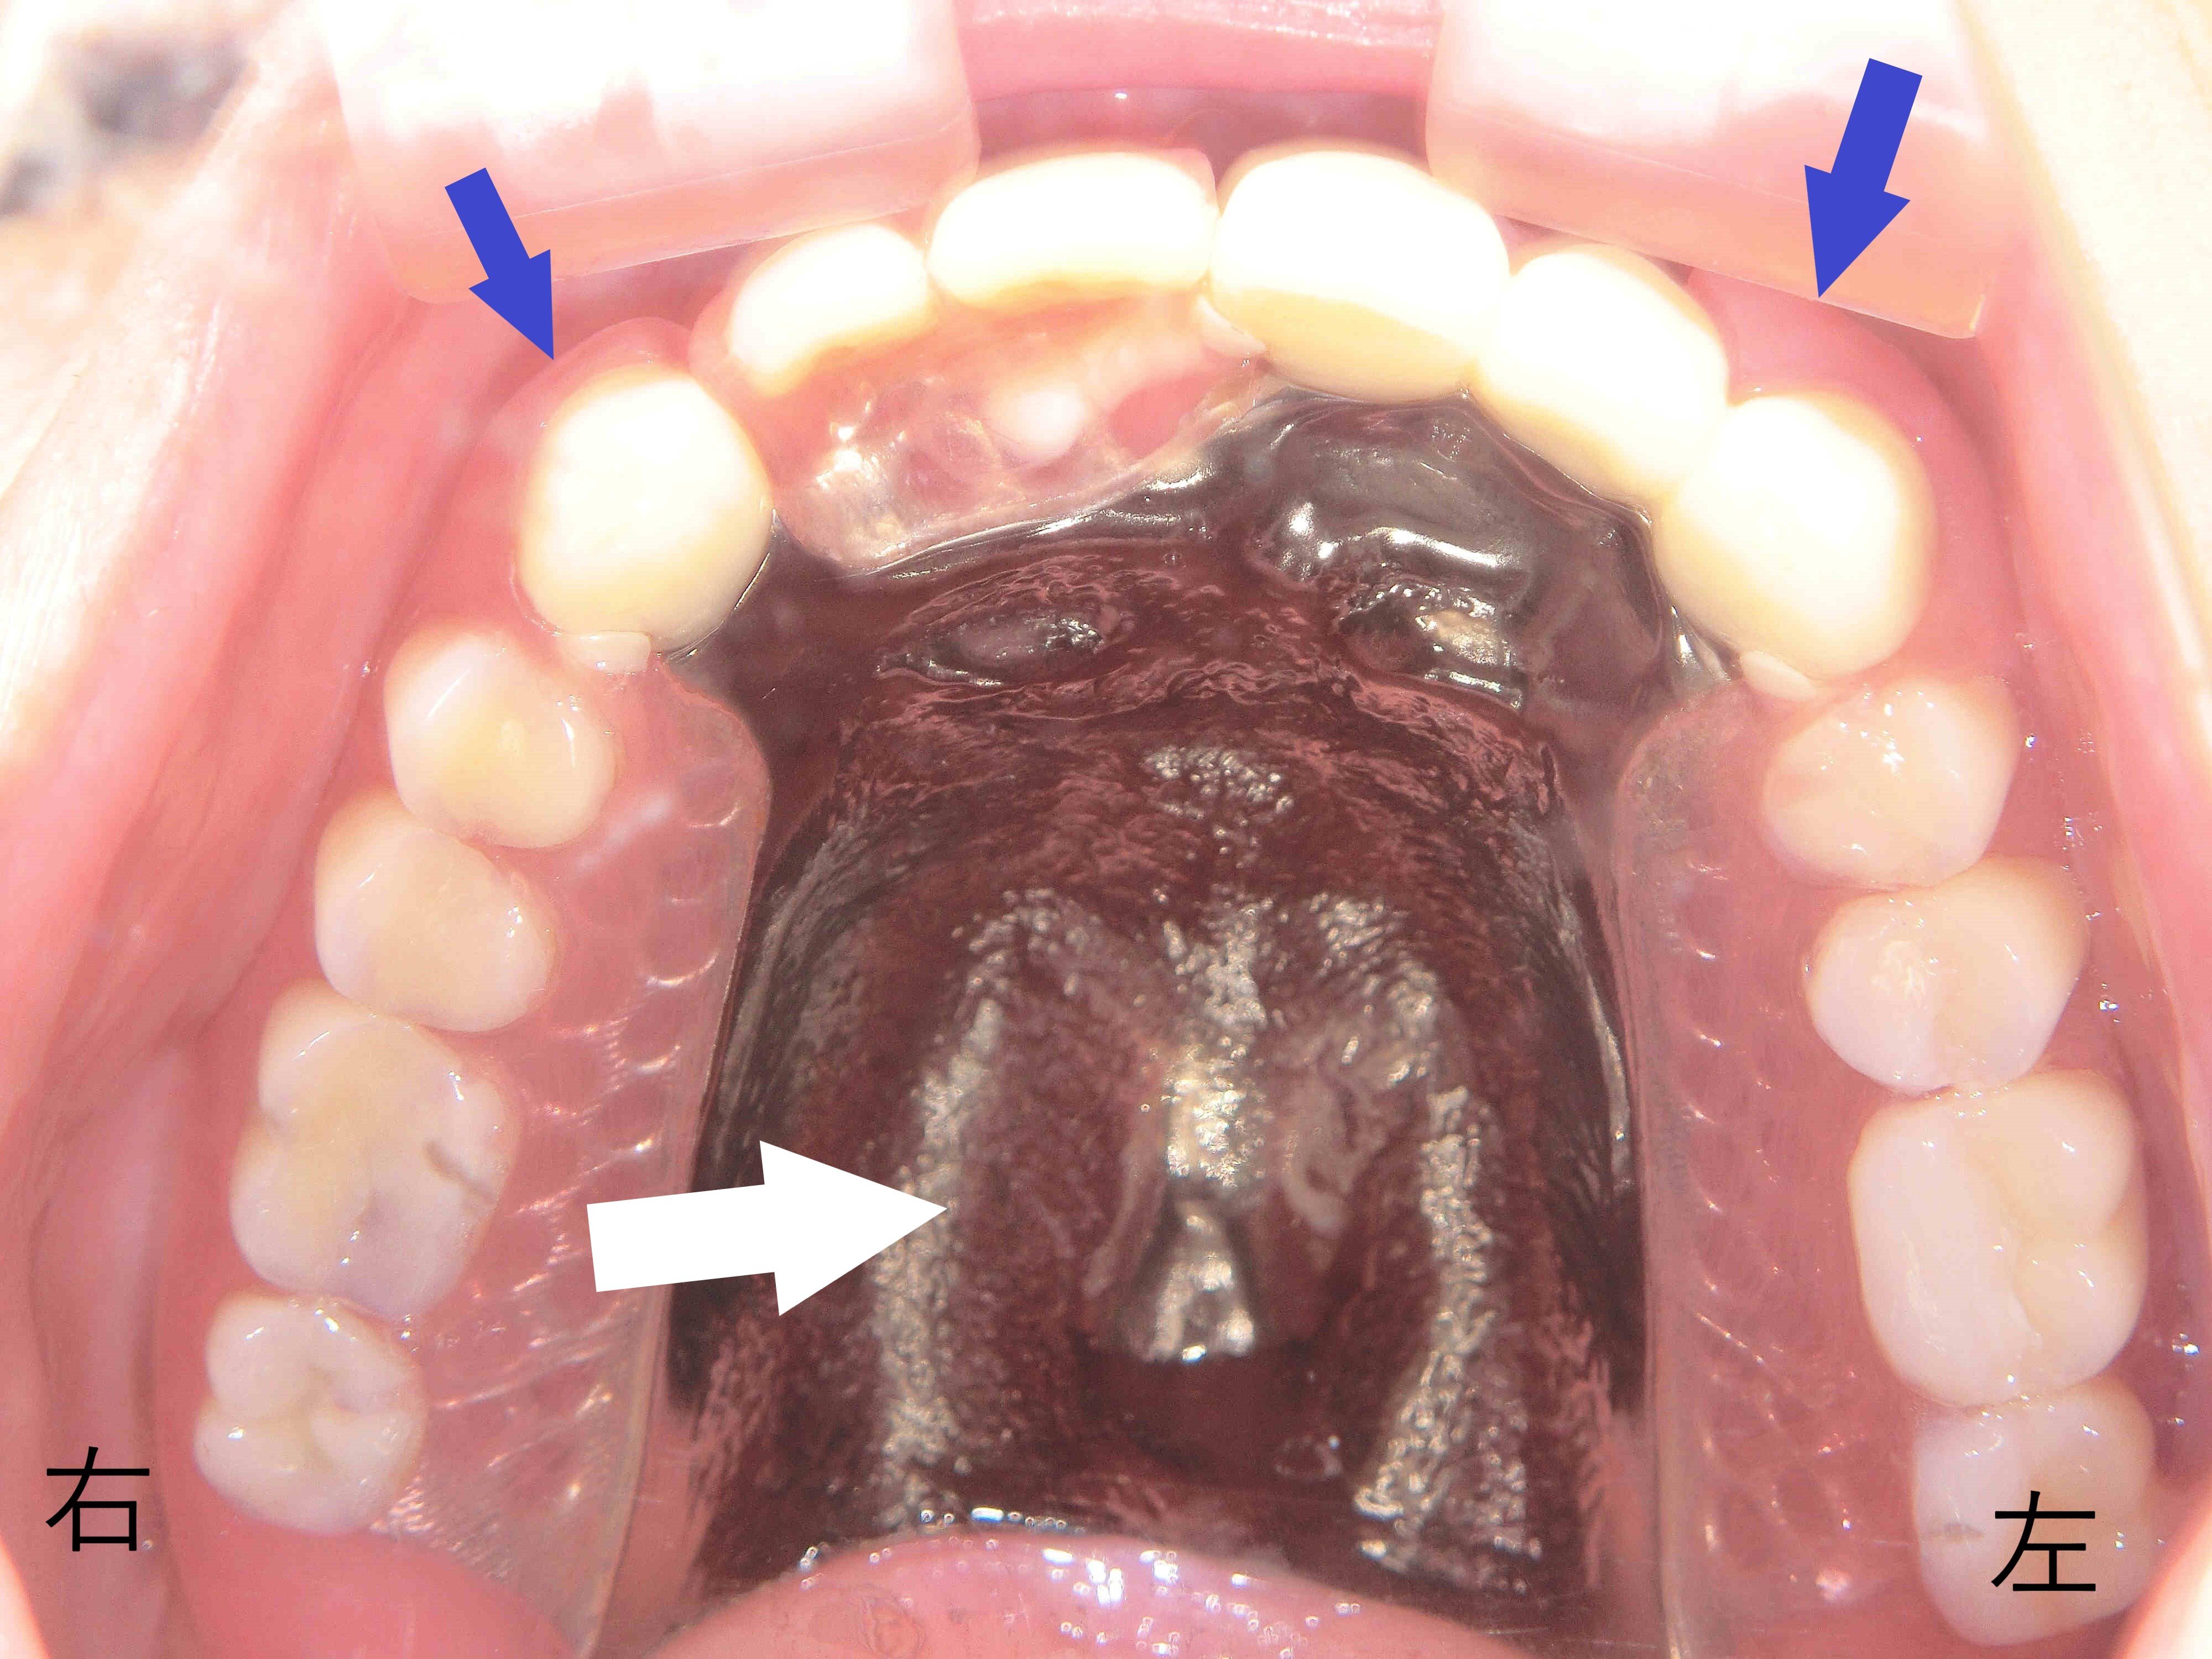

上顎に金属のバネを使用しないノンクラスプデンチャーを装着した状態を正面から撮影した写真では、歯ぐきと似た色の樹脂製のバネが用いられており、前述の保険義歯と比較して審美性が大幅に向上しています(青色矢印)。

また、口蓋部には保険義歯に使用される樹脂ではなく、チタン製の金属床が用いられており、義歯を薄く仕上げることができています。

患者様からも「薄くなって話しやすくなり、違和感が少なくなった」との感想をいただいております(※個人の感想です)。